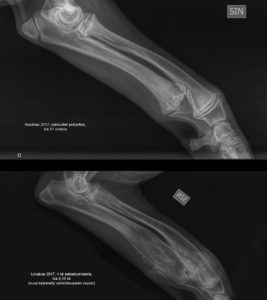

Otetaanpa vielä vertailukuva jaloista kesäkuun ja lokakuun tilanteeseen:

Verrokkikuvassa lokakuun kuva on käännetty vertailtavuuden vuoksi.